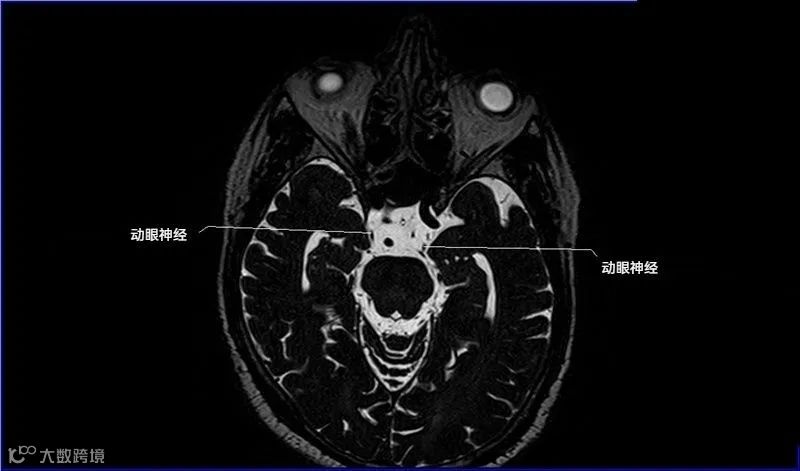

十二对脑神经口诀

一嗅二视三动眼,四滑五叉六外展,

七面八听九舌咽,迷走及副舌下全。